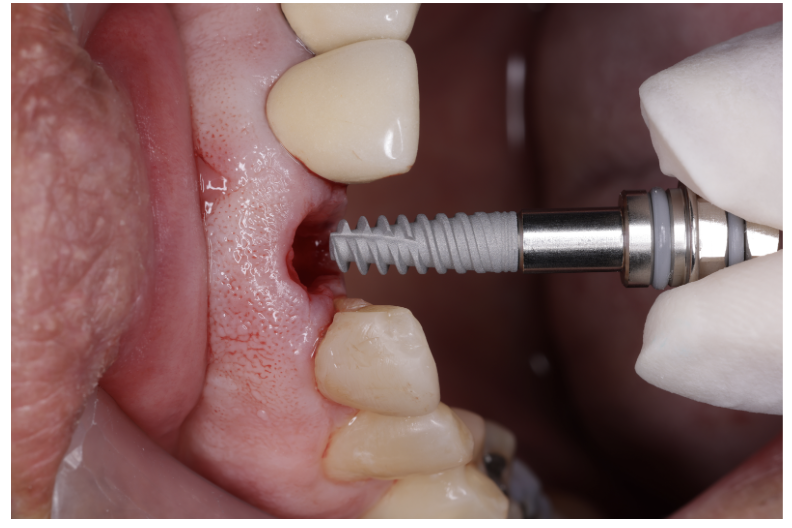

- Cirugía de colocación del/los implantes.

¿Qué es la implantología?

La implantología es la especialidad que reemplaza dientes perdidos mediante tornillos de titanio (implantes) que actúan como raíces artificiales. Permiten soportar coronas, puentes o sobredentaduras, devolviendo la masticación, el habla y la estética con resultados naturales y previsibles.